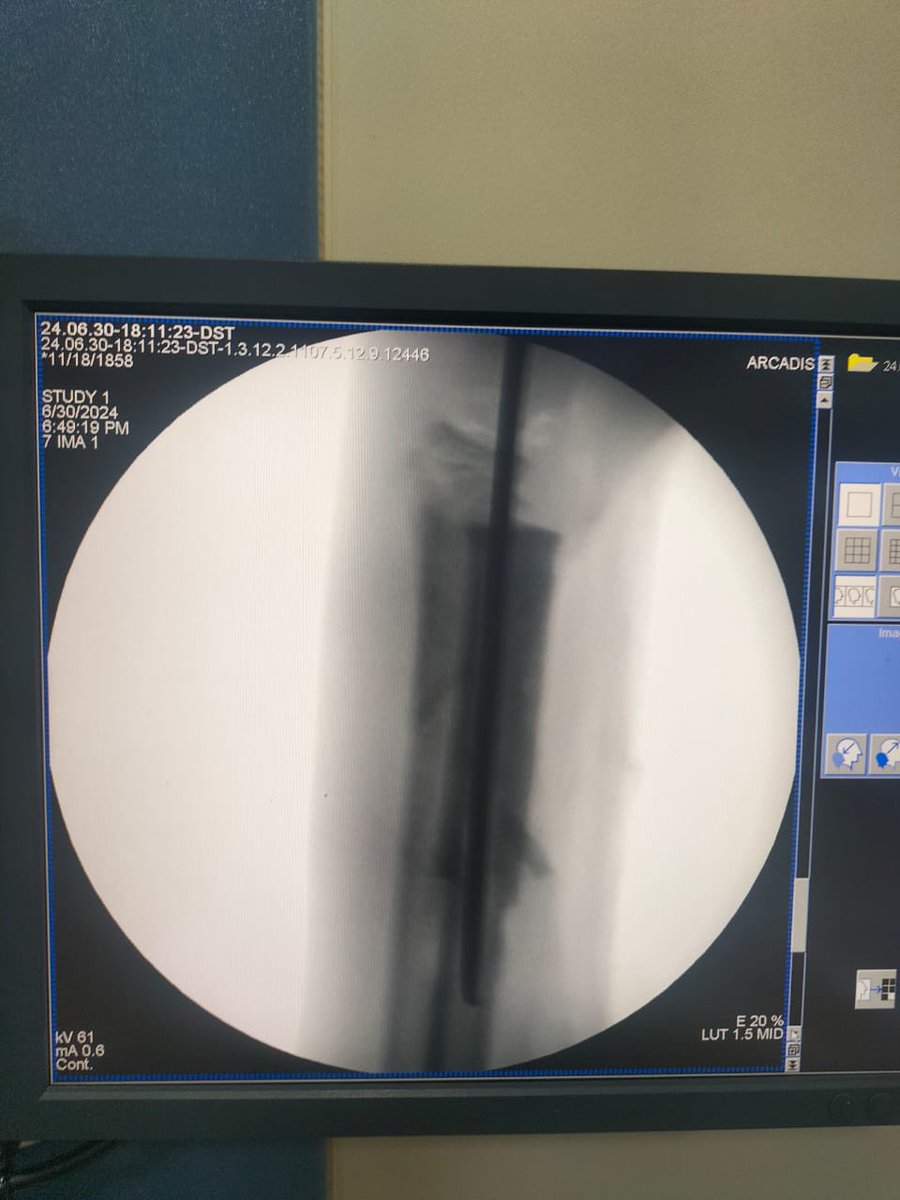

تم استئصال العظام الميتة و تركيب اسمنت طبي مؤقت لحين التأكد من انتهاء الصديد ثم عمل ترقيع للعظم.